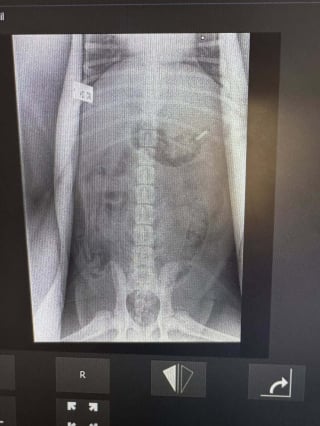

Il a donc été décidé d’attendre le lendemain pour s’assurer de la présence de l’objet dans l’estomac en effectuant une radiographie. Cette dernière a confirmé les suspicions des propriétaires du chiot, montrant clairement la lame.